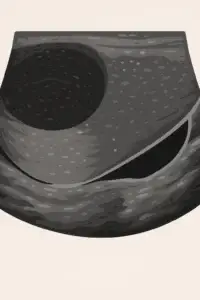

Scrotal Imaging

Scrotal imaging is often the first imaging study performed in men with fertility concerns. The scrotum houses the testicles, epididymis, and other structures critical for sperm production and transport, so assessing scrotal anatomy is essential.

- Purpose: Scrotal imaging is used to examine the testicles, epididymis, and surrounding structures for abnormalities such as varicoceles (enlarged veins in the scrotum), hydroceles (fluid-filled sacs around the testicle), cysts, or testicular masses.

- Indications: Scrotal imaging is recommended when there are concerns about structural abnormalities (e.g., palpable masses, testicular pain, or swelling) or when initial semen analysis results indicate potential sperm transport or production issues.

- Preferred Modality: Ultrasound is the first-line choice for scrotal imaging. It provides high-resolution images without radiation, is cost-effective, and is widely accessible. Using spectral Doppler and elastography, testis function can also be evaluated.